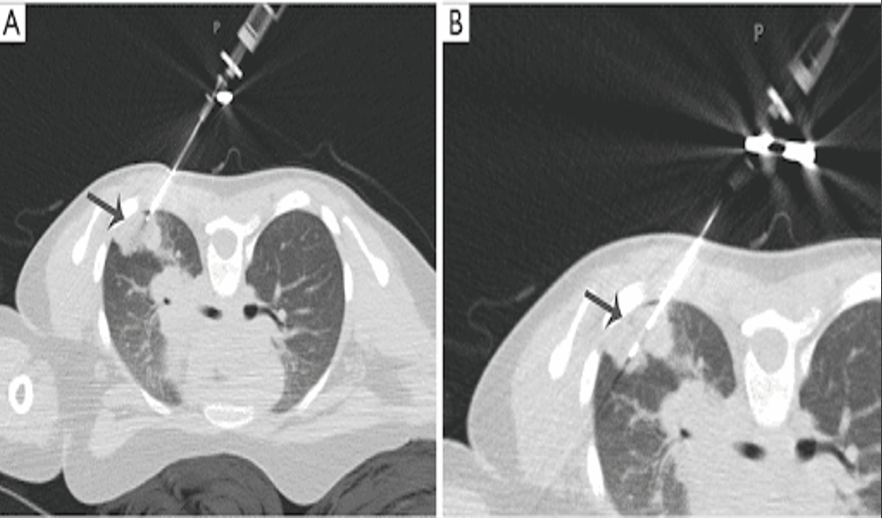

transthoracic needle biopsy

peripheral lesions away from diaphragm

25% chance of pneumothorax

benefit for patients who are poor operative candidates

negative needle biopsy may be a false negative